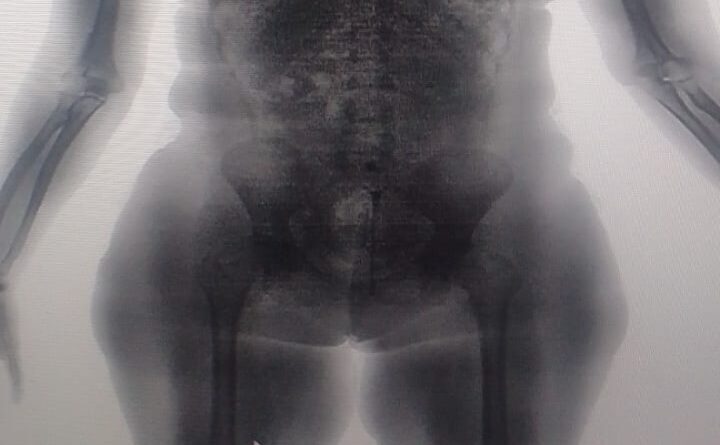

Uma mulher foi presa ao tentar acessar com drogas o Conjunto Penal de Lauro de Freitas, na Região Metropolitana de Salvador (RMS). Por meio de imagens do equipamento BodyScan, os policiais penais identificaram substâncias análogas à maconha e à cocaína escondidas no corpo da visitante, que tentou burlar o procedimento padrão de revista.